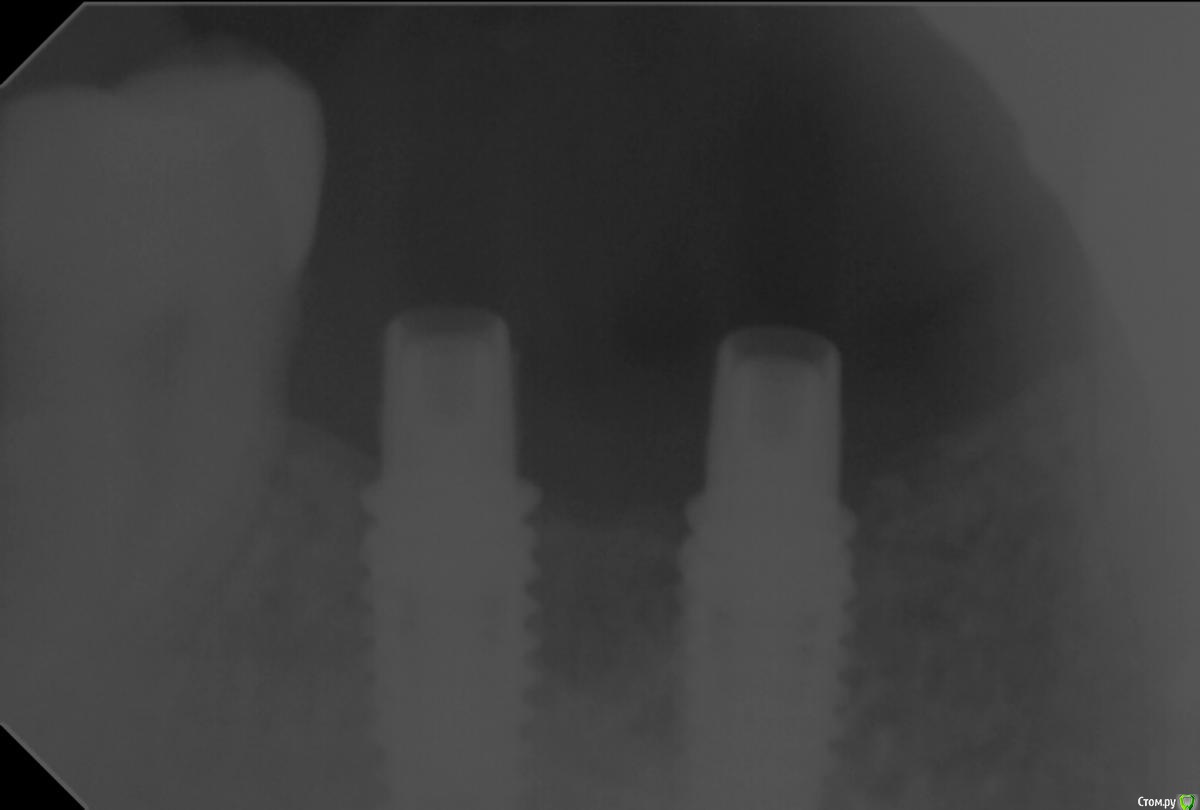

Freelancer1981 Опубликовано 11 апреля, 2016 Автор Поделиться Опубликовано 11 апреля, 2016 Снимок будет? Ссылка на комментарий

АнтонТЛТ Опубликовано 11 апреля, 2016 Поделиться Опубликовано 11 апреля, 2016 Это максимальное качество снимка? Абатменты чьи? Ссылка на комментарий

Freelancer1981 Опубликовано 11 апреля, 2016 Автор Поделиться Опубликовано 11 апреля, 2016 Да,лучше не получится,наверное,абатмены необиотек. Ссылка на комментарий

АнтонТЛТ Опубликовано 11 апреля, 2016 Поделиться Опубликовано 11 апреля, 2016 Должны нормально садитьсяhttp://i78.fastpic.ru/big/2016/0411/b9/8c181fc4a248de1ac7776219126e03b9.pngСкорее всего мешают мягкие ткани. Попробуйте закрутить на 20 Нсм. Если при затягивании стопорится, то досело. А если ощущение, что на 20 Нсм можно крутить дальше, то мешают мягкие ткани. По снимку это не временные абатменты. Ссылка на комментарий

Freelancer1981 Опубликовано 11 апреля, 2016 Автор Поделиться Опубликовано 11 апреля, 2016 при затягивании стопорится,ишемии минимальна так как мягкие ткани были на формиках сформированы нормально,мягкие ткани отпадают,может винты взять оригинальные?что по снимку скажете?P/s/абатменты конечно постоянные,коронки временные Ссылка на комментарий

АнтонТЛТ Опубликовано 11 апреля, 2016 Поделиться Опубликовано 11 апреля, 2016 Тогда и абатменты от Anyone, винты от одной системы могут не подходить к абатментам другой системы.Снимок не в той проекции сделан, надо под 90 градусов делать. Ссылка на комментарий